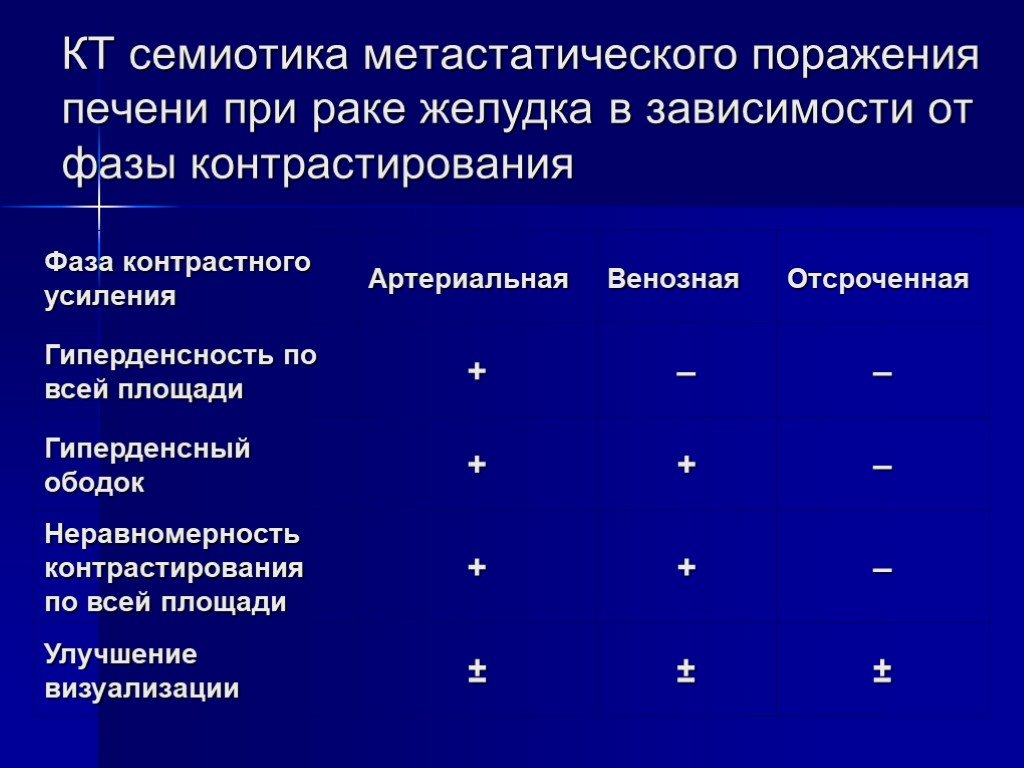

Метастатические поражения печени в ультразвуковом изображении характеризуются